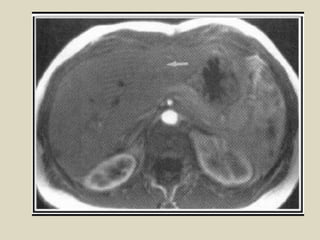

Magnetic resonance imaging (MRI) was discovered in 1947 by two physicists and the first clinical images were obtained in 1977. MRI uses strong magnetic fields between 1-9 Tesla to align hydrogen atoms in the body and radio waves to elicit signals to form images. The document provides a brief history of MRI and discusses magnetic fields, relaxation processes, and pulse sequences used to generate MRI images.